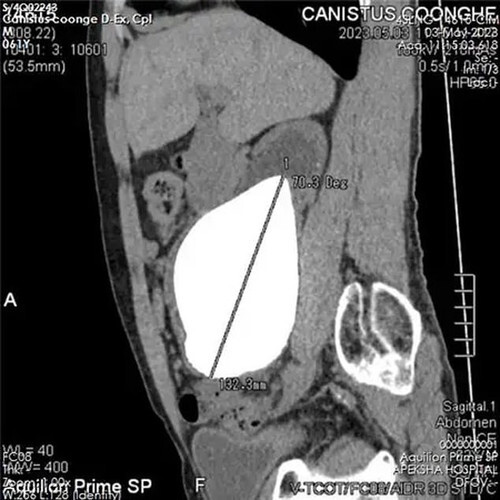

Мазок на инфекции, УЗИ, Сумамед "на всякий случай". Мазок - это тоже больно. Это такой ёршик, который тебе прямо туда засовывают. Но не так больно, как писать. Анализы хорошие, а вот УЗИ... Песочек у меня. Не камни - много мелкой фракции. Видимо что-то покрупнее проскочило наружу, оцарапало мочеточник, воспалилось и теперь болит.

Что делать? Пейте толокнянку по паре столовых ложек в качестве мочегонного. И ждите пока всё выйдет. Потом снова на УЗИ. И я пью. Неделю пью. Две пью. Болит уже не только член. Больно теперь еще и внутри. Иду снова к доктору. Снова УЗИ.